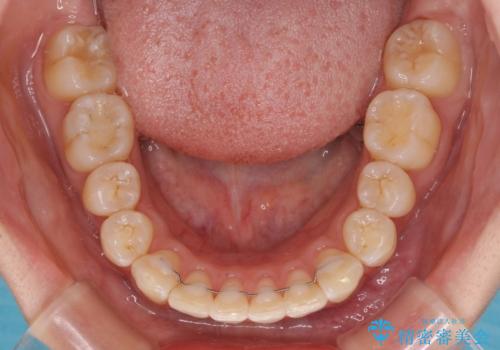

- 口を閉じたときに唇の間から飛び出してくる前歯を気にして来院された患者様です。

骨格的に上顎骨が前方位にあるため、左右の第一小臼歯を抜歯し、ワイヤー装置にて咬み合わせを整えていくこととしました。

前歯の突出感が改善されるだけでなく、奥歯の咬み合わせも改善され、食いしばりをしにくい状態に仕上げることができました。